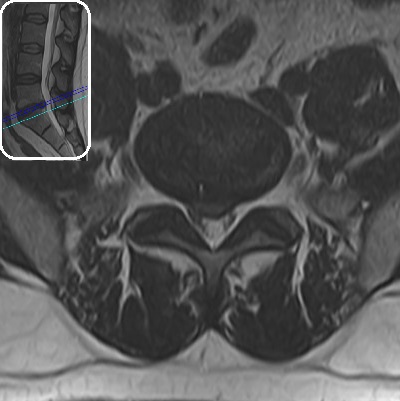

Lomber MRG İncelemesi - L5-S1 Bulging Lomber MRG İncelemesi - Dejeneratif Disk Hastalığı

Resim 1: Lomber MRG incelemesinde L5-S1 seviyesinde santral bir bulging görülmektedir. Sağ S1 köküne dokunacak şekilde anulus fibrozusta küçük bir açıklık ve ufak bir ekstrüde fragman varlığından şüphe edilebilse bile, kesin söylenemez. Aynı seviyede disk içi hipointens ve komşu L5 vertebrası alt endplate'i ön kısmında dejeneratif sinyal değişikliği görülmektedir (dejeneratif disk hastalığı). Lomber lordoz korunmuştur. Diğer disk seviyeleri, faset eklemler ve paravertebral kaslarda belirgin bir sorun saptanmamıştır.